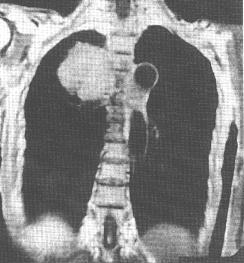

3.MRI 骨骼系統的病變為破骨性溶骨性、部分溶骨和部分硬化性及骨皮質的改變等多種表現。MRI對於原發性骨淋巴瘤的診斷敏感性較高,能發現其他檢查陰性的原發性骨淋巴瘤。同時它能發現周圍結締組織的病變。